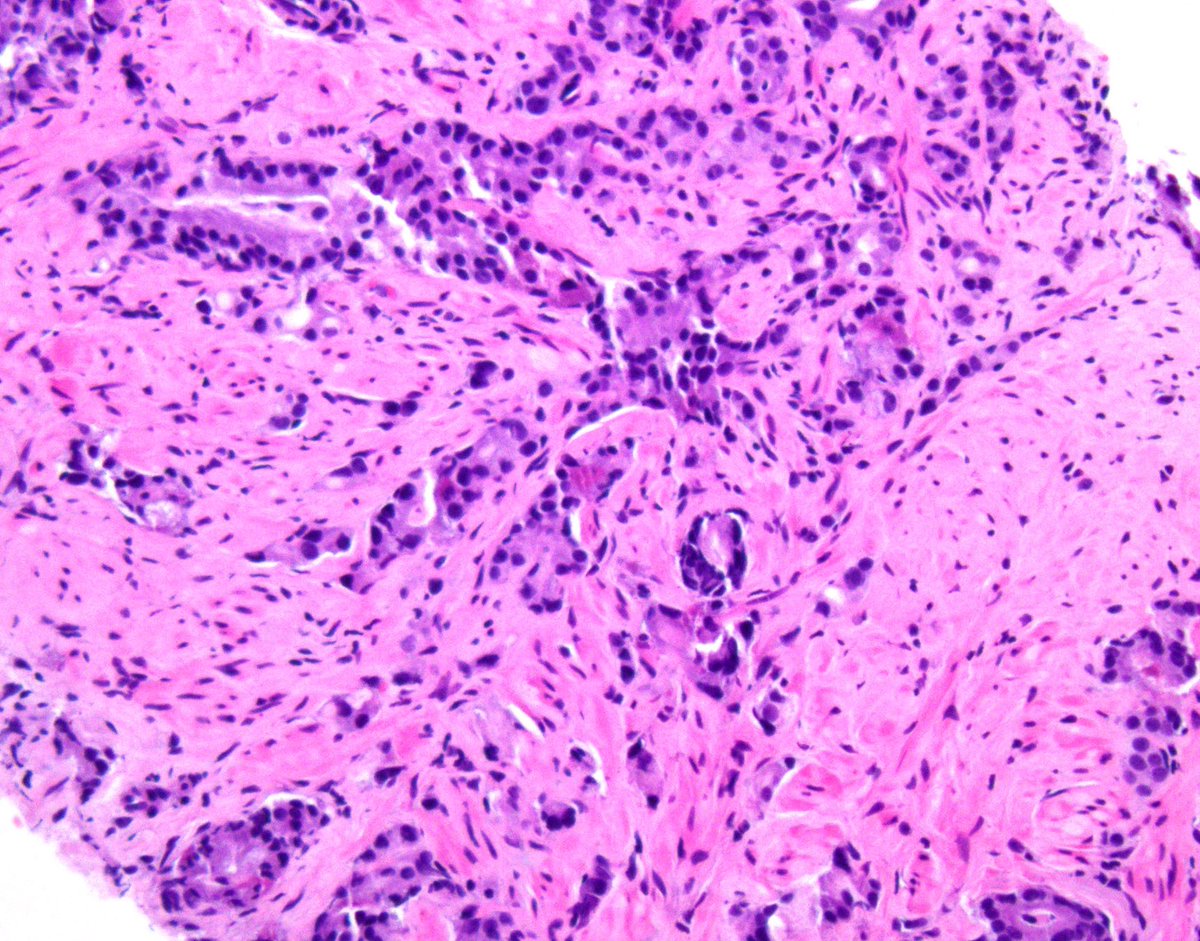

@GladellPaner

Tubulocystic renal tumor with a twist. 👀 What’s your top diagnosis #GUPath tweeps? #OnePicDx Answer in comment. 👇🏻👇🏻👇🏻

3

28

118